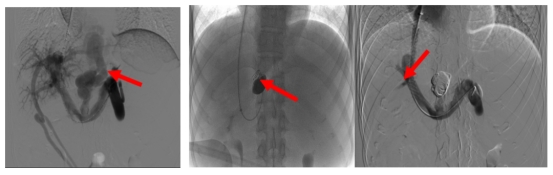

喜报 | +4!广医五院1项重大技术、3项特色技术入选广州地区临床高新、重大和特色技术!

近日,广州市卫生健康委公布了广州地区临床高新、重大和特色技术(2026—2028年)项目名单。